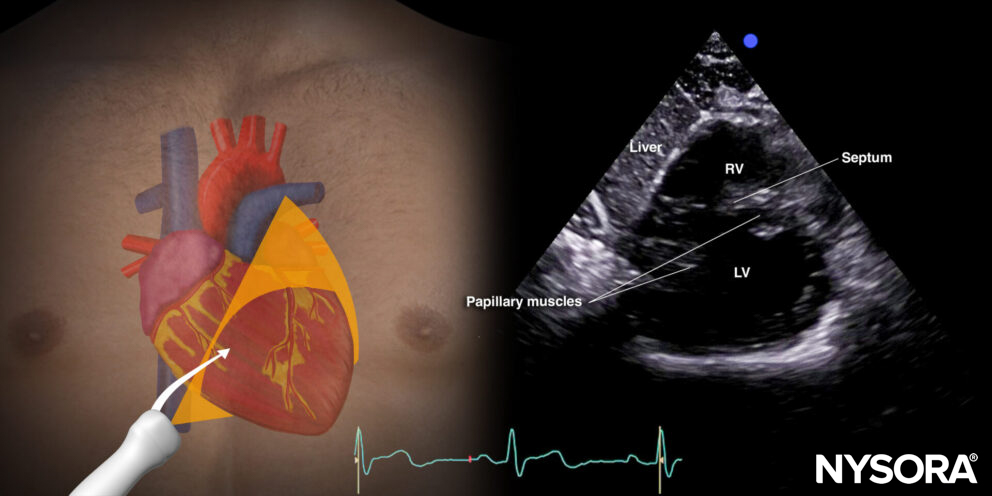

The standard parasternal short-axis view cuts the heart through the transverse plane.

Sonoanatomy of the heart in the parasternal short-axis view. Right ventricle (RV), septum, left ventricle (LV), and papillary muscles.

Reverse ultrasound anatomy:

Reverse Ultrasound Anatomy of the heart in the parasternal short-axis view. Right ventricle (RV), septum, left ventricle (LV), and papillary muscles.

C. Papillary muscle level or standard parasternal short-axis view: Right ventricle, left ventricle, papillary muscles (posteromedial and anterolateral papillary muscle).